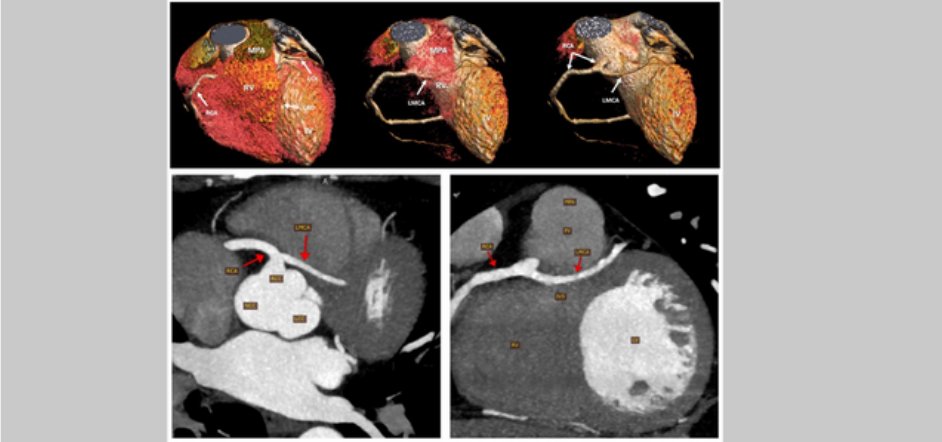

#ImageoftheWeek This #quiz was submitted by Mahmoud Naseem Shaaban from the Aswan Heart Centre (Magdi Yacoub Foundation), Aswan, 🇪🇬 What is the course of this anomalous (LMCA) originating from the right coronary artery (RCA)? ☑️shorturl.at/6f8Dr @EACVIPresident

echo_stepbystep's tweet image. #ImageoftheWeek This #quiz was submitted by Mahmoud Naseem Shaaban from the Aswan Heart Centre (Magdi Yacoub Foundation), Aswan, 🇪🇬

What is the course of this anomalous (LMCA) originating from the right coronary artery (RCA)?